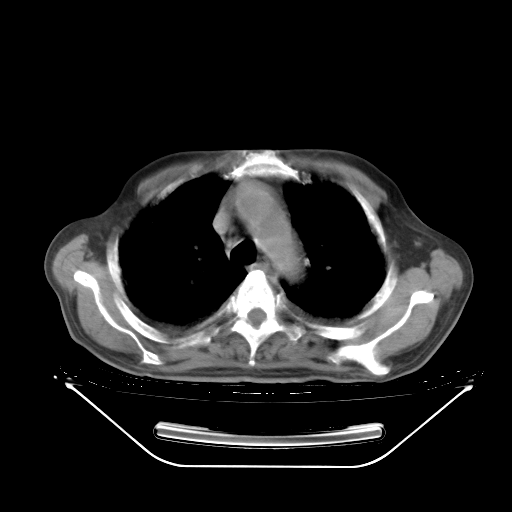

胸腹部CT,诊断意见:左上肺叶钙化灶、左侧胸膜局限性增厚并钙化、胆囊炎。描述部分肺组织呈磨玻璃样改变。